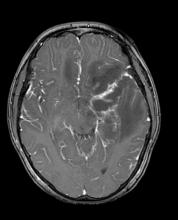

Acute pneumocephalus in neurosurgical patients operated on in supine and prone position

Acute post-surgical pneumocephalus is frequent in patients with cranioencephalic pathology operated on in the supine and prone position. The distribution and degrees of pneumocephalus may be related to sex, the type of cranioencephalic pathology, and the depth of the surgical lesion.